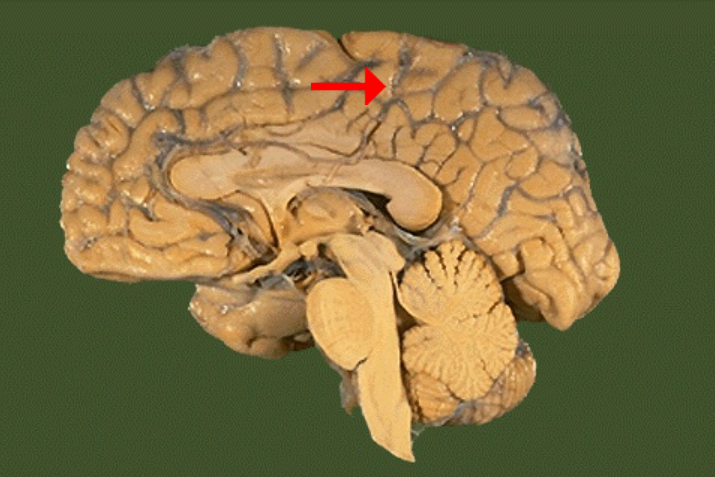

Label this brain part

Frontal lobe

Label this brain part

Parietal lobe

Label this brain part

Occipital lobe